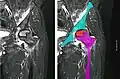

Femoral head showing a flap of cartilage due to avascular necrosis (osteochondritis dissecans). Specimen removed during total hip replacement surgery.